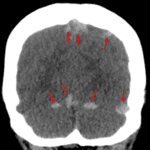

- Hyperattenuating appearance of the superior sagittal sinus, straight sinus, bilateral tentorial and cortical veins, both transverse sinuses, and the confluence of sinuses

- Dural venous sinus thrombosis

Findings concerning for thrombosis of the superior sagittal sinus, straight sinus, bilateral tentorial and cortical veins, both transverse sinuses, and the confluence of sinuses. Recommend brain MRI with and without contrast for further evaluation.